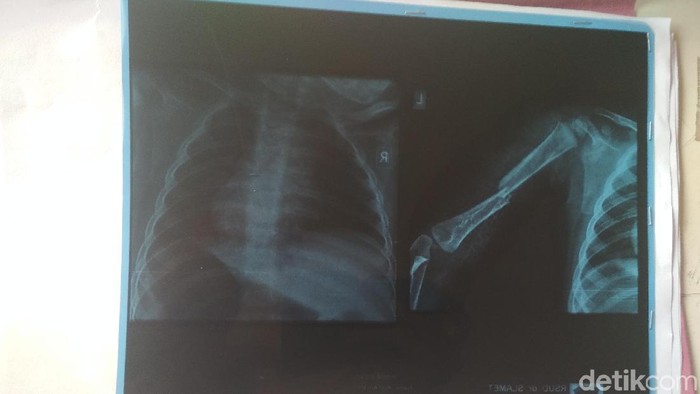

"Kemudian terjadi lah tangan kiri si anak ini dipelintir oleh tersangka hingga patah," ujar Budi.

Kala itu keluarga langsung membawa sang anak ke puskesmas terdekat. Beruntung, sang anak langsung mendapat pertolongan dan dapat diselamatkan.